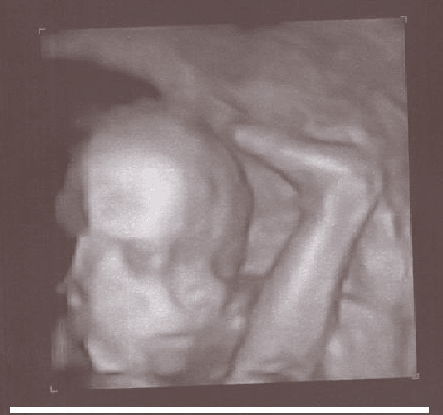

Anielka chciała się przywitać - zdjęcie z dzisiaj, czyli koniec 26 tygodnia :) Nochal trochę rozciągnięty, bo się ruszyła ;)

I dla porównania Franek w 4 dobie życia - ten sam profil, dolna warga zapadnięta, zaokrąglony na końcu nosek ;)

Zawsze myślałam, że ten widok na usg nie ma nic wspólnego z rzeczywistym obrazem a u Ciebie Ewa rzeczywisty klon :rofl2::-D

ewa ale czad :-D Normalnie malusia replika braciszka. Fajna sprawa takie porównanie. Ja podobnie jak kakakarolina byłam pewna, że obraz takiego zwyczajnego USG niewiele się ma do rzeczywistości, a tu proszę :tak:

Ewa dołaczam się do dziewczyn- porównanie nieziemskie takie podobieństwo- super;-)

ewa, rzeczywiście klony dwa :-)